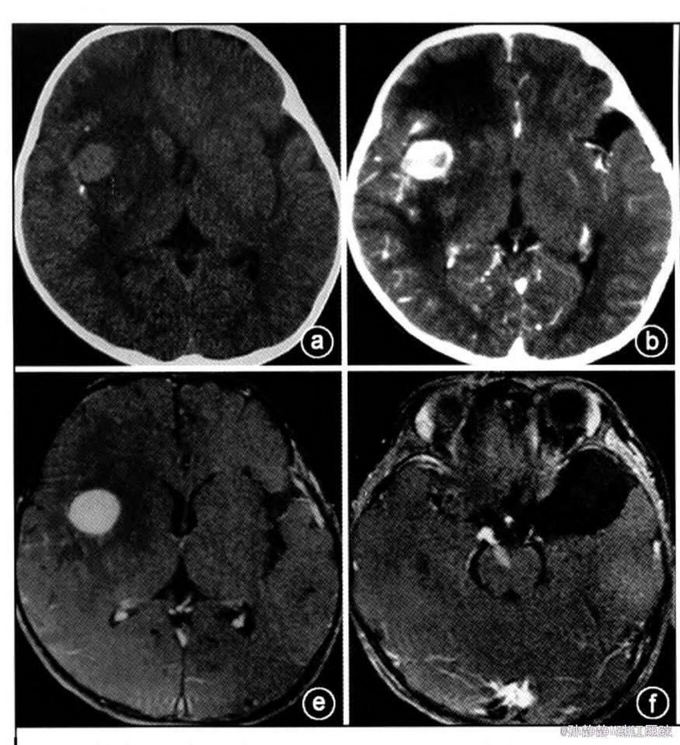

辅查:眼底检查示双侧乳头水肿,颅脑CT示右额叶等密度占位,伴钙化。增强后明显强化,约2厘米。增强MRI T1加权呈等信号,T2 加权等或稍低信号。脑桥、右顶叶也可见病灶,病灶周围可见水肿。

初步诊断:颅内感染性肉芽肿:淋巴瘤?结核?白血病脑病? 处理:考虑患儿有明显颅内压增高症状,行右侧扩大翼点入路开颅手术,切除右额叶明显病变。病理示明显新生血管形成和炎性细胞浸润,部分见组织细胞,核为肾形,疑为朗格汉斯细胞。免疫组化CD68及波形蛋白阳性。S-100及Cd 1a部分细胞阳性。 确诊:颅内朗格汉斯增生症。